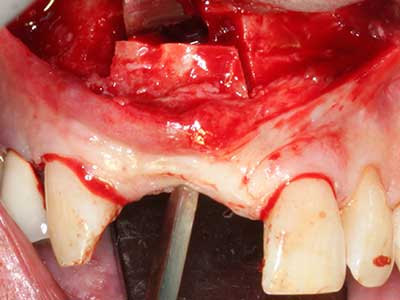

Indication: Bone splitting

Bone tissue is not simply a mineral structure but also contains a substantial proportion of collagen fibres. This means it not only has good compressive strength but also a degree of flexibility, which can be taken advantage of when performing bone augmentations. In the classical expansion procedure using bone splitting, the atrophied alveolar ridge is split longitudinally and carefully expanded after reaching an adequate osteotomy depth (Fig. 13-16), ideally without substantial removal of the periosteum (Brugnami, Caiazzo et al. 2014, Stricker, Fleiner et al. 2014). Screw and plate systems with increasing expansion distance have proven effective in separating the two bone lamellae while remaining below the fracture threshold. In general, residual bone widths of at least 3–4 mm are required (Chiapasco, Zaniboni et al. 2006) to guarantee adequate flexibility and sufficient bone coverage of the future implants. If necessary, a vertical relief osteotomy on one or both sides can improve flexibility. A combination with additional augmentation techniques, particularly on the buccal side, has been described as an alternative to the classical technique.

The splitting procedure is particularly atraumatic and there is no significant loss of dimension when using piezosaws, and there are no significant differences between implants in split jaws and implants in an alveolar ridge without a bone deficit (Chiapasco, Zaniboni et al. 2006, Danza, Guidi et al. 2009). However, sufficient continuous irrigation is essential, particularly with locally restricted and deep splitting to prevent thermal stress in the apical osteotomy regions.